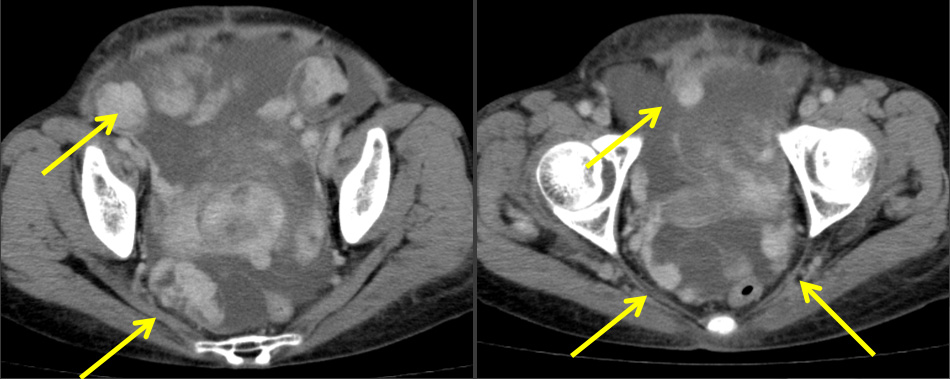

CT

- 骨盤部ほぼ正中に存在する不整形腫瘤。

軟部組織濃度で、内部に不均一な低吸収域がみられる。

- 不均一な造影効果あり。

- 胸水(右優位) 腹水

Dedifferentiated solitary fibrous tumor (SFT) in the pelvis

術後5カ月 手術+化学療法後再発

胸膜、腹腔内、腹膜に播種性に再発